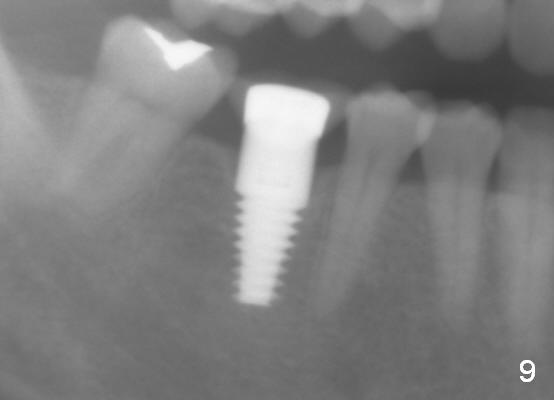

Six years ago, a 38-year-old patient presented to our office for new patient exam. She was scared of dentistry, but 3 of the third molars needed extraction. When the surgery was done painlessly, it was not too hard to persuade the patient to accept implant placement at the site of #30 (Fig.1; N: Inferior Alveolar Nerve). It was the 1st case when a 2nd implant system was adopted in the office. The implant is 3 mm shorter than the design (Fig.2). An incision was made for visibility (Fig.3). There is no bone loss 3.5 months postop (Fig.4). The crown is cemented 5 months postop (Fig.5); there is attached gingiva buccal to the implant. What surprised us the most is that she turns out to be one of the most faithful patients in our office. She never misses 6-month recall.

Fig.6-8 show images taken 6, 21 and 34 months post cementation. Bone remains stable 6 years postop (Fig.9).